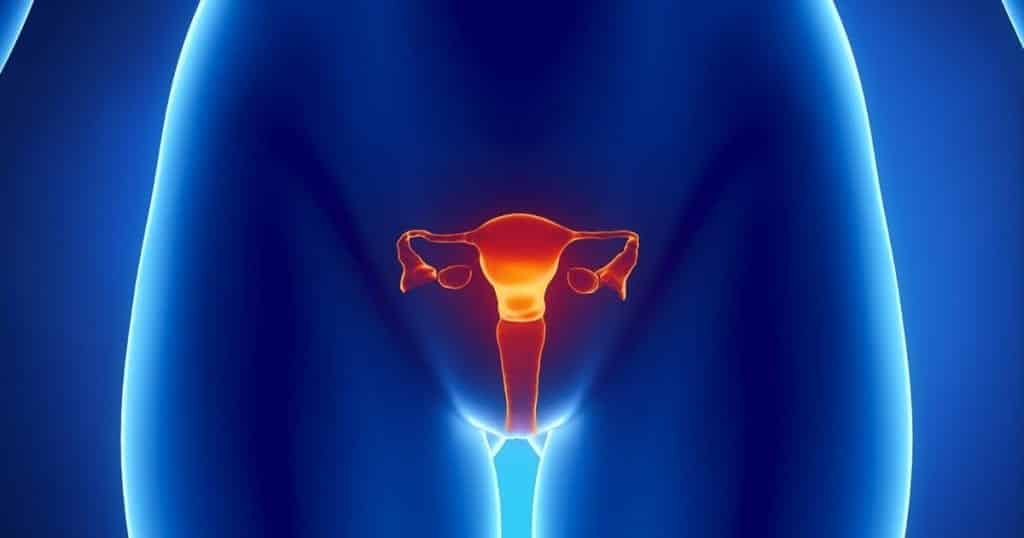

Órgãos do Sistema Reprodutor

O sistema reprodutor é o sistema responsável pela nossa reprodução. Sendo assim, o sistema reprodutor feminino garante a formação dos gametas femininos e a gestação do bebê. E o sistema reprodutor masculino é responsável pela produção e transferência do gameta masculino para a mulher.

Assim sendo, vamos conhecer melhor os órgãos do corpo humano que compõe desse sistema:

Órgãos do Sistema Reprodutor Feminino

- Ovários: são dois órgãos em forma oval localizados na cavidade pélvica das mulheres. Portanto, sua função baseia-se na produção do hormônio feminino, o estrógeno, bem como na produção dos óvulos, os gametas sexuais femininos.

- Útero: localizado no interior da cavidade pélvica, o útero é um órgão muscular, oco e elástico. Desse modo, ele é responsável pela menstruação, gravidez e parto. Sendo assim, sua principal função é abrigar o feto depois de fecundado.

- Clitóris: é o órgão sexual erétil feminino e está localizado na parte superior da vulva. Desse modo, sua função principal é proporcionar o prazer feminino (orgasmo), visto que sua estrutura é formada por inúmeras terminações nervosas.